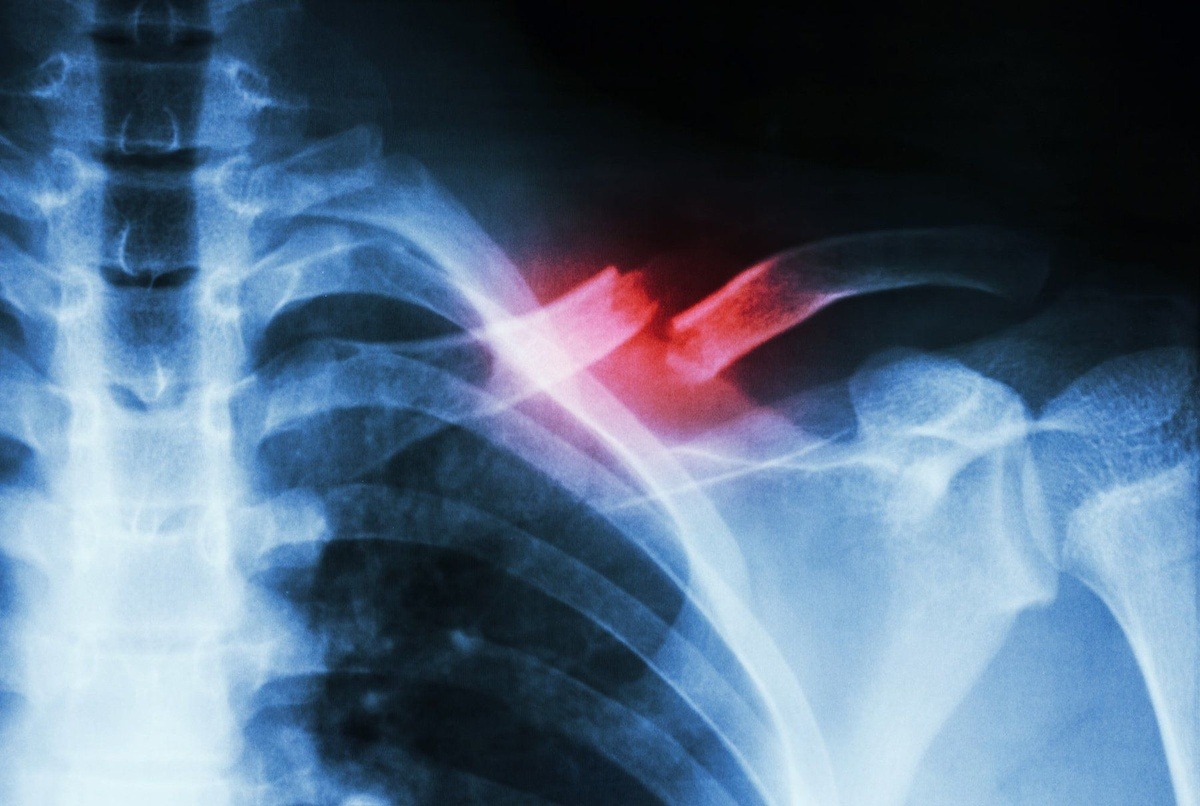

Nạn nhân là bà L.T.L (sinh năm 1958, trú tại Nông Cống, Thanh Hóa), được người nhà đưa đến Phòng khám chuyên khoa Ngoại Bs Dương Văn Thọ (số 69 Lê Thánh Tông, phường Đông Vệ, TP Thanh Hóa) vào khoảng 11h ngày 28/5/2025 để điều trị gãy xương đòn. Phòng khám này được Sở Y tế Thanh Hóa cấp phép hoạt động từ ngày 23/9/2022, do Bác sĩ Dương Văn Thọ phụ trách chuyên môn.